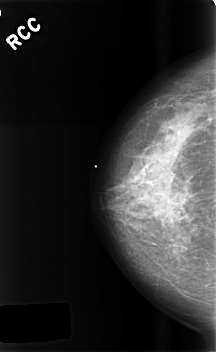

C_0466_1.RIGHT_CC

RIGHT_CC LINES 4576 PIXELS_PER_LINE 2808 BITS_PER_PIXEL 12 RESOLUTION 50 NON_OVERLAY